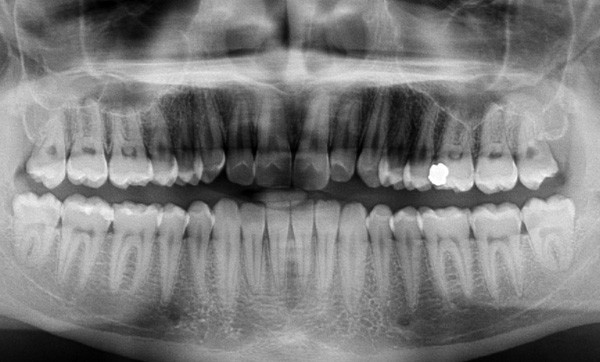

En intra-arcades (fig. 4-6), on note une classe III molaire et canine (fig. 4-5), trois plans d’occlusion, une déviation des milieux d’origine mandibulaire et un inversé articulé du bloc incisif maxillaire ; le biotype parodontal est fin, et l’on note des récessions gingivales (12, 13, 23, 33, 43) certainement dues à la mauvaise position et aux forces mal réparties lors de la mastication (fig. 5). L’arcade maxillaire est carrée avec une DDM antérieure (fig. 7), l’arcade mandibulaire étroite et allongée (fig. 8).